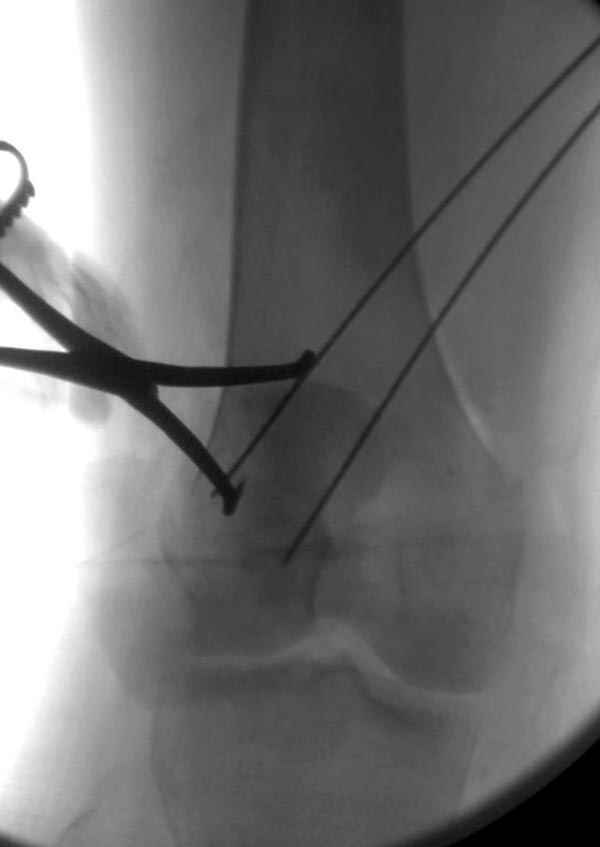

Сегодня досылаю остальные снимки, которые не прошли вчера. Как вчера писал, после фиксации перелома надколенника с дефектом кости и собственной связки, наложили ваккуум и наружный фиксатор. (снимки 4-9)

Внешний фиксатор держим около 6 недель, поэтому был выбран метод фиксации шурупами и еще линия перелома была диагональной, не было нужды в tension band technique, cannulated screws удобнее, провел спицы и по ним шурупы.